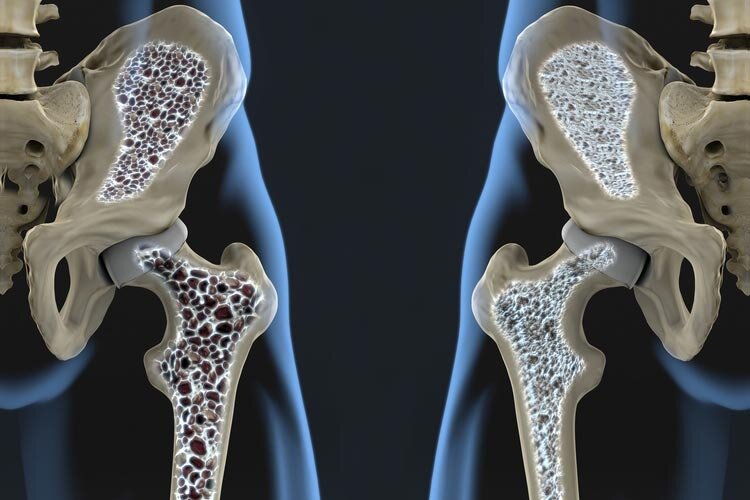

افزایش قابل توجه پوکی استخوان پس از ۵۰ سالگی ۱۴.۰ | مطالب پیشنهادی (مشابه) | ذخیره شده

۲۰ مهر ۱۴۰۰ — افزایش قابل توجه پوکی استخوان پس از ۵۰ سالگی

افزایش قابل توجه پوکی استخوان پس از ۵۰ سالگی ۱۴.۰ | مطالب پیشنهادی (مشابه) | ذخیره شده

۲۰ مهر ۱۴۰۰ — افزایش قابل توجه پوکی استخوان پس از ۵۰ سالگی